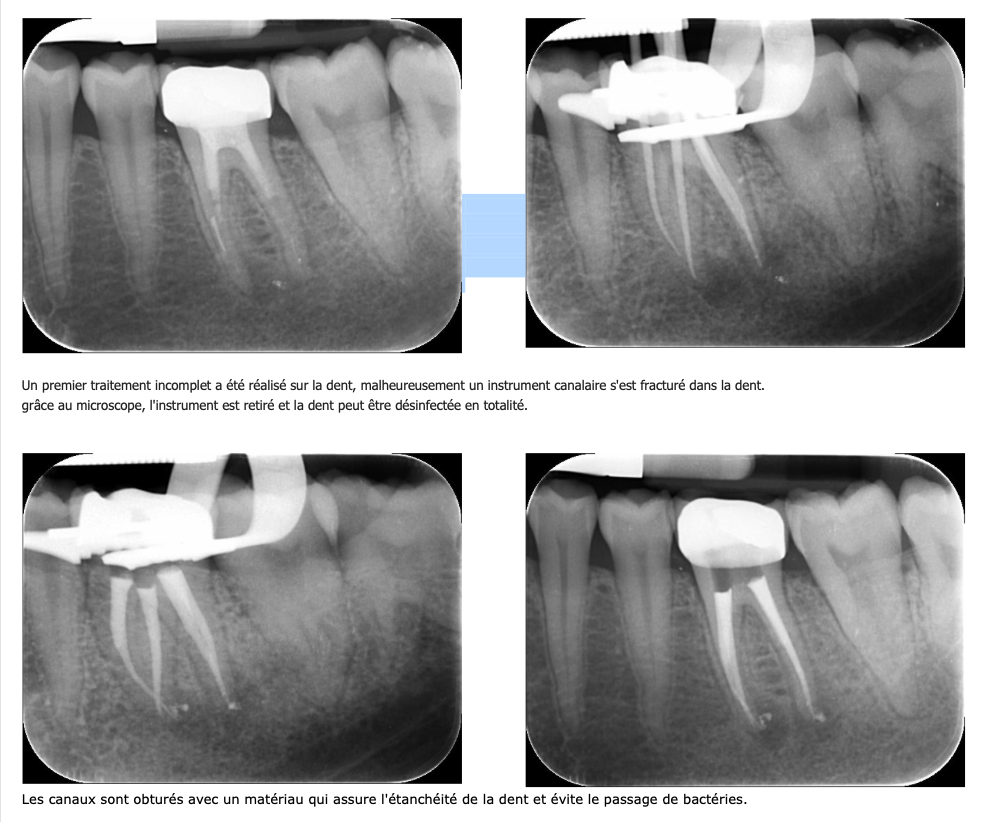

Quand le premier traitement réalisé n’est pas satisfaisant, un retraitement est à envisager afin de traiter ou prévenir la formation d'un kyste.

Ce type de lésion osseuse apparait, lorsqu'une petite partie du canal n'est pas désinfectée et obturée. Il est indispensable que tout le volume canalaire de la dent soit nettoyé et obturé.

Après avoir éliminé le matériau d’obturation existant et après avoir contourné les différents obstacles (démontage des prothèses et/ou des tenons, suppression des fragments d’instruments fracturés dans le canal, récupération des trajectoires canalaires, etc…), tous les canaux sont à nouveau nettoyés, désinfectés et obturés.

présence d’un instrument fracturé lors du traitement préalable,